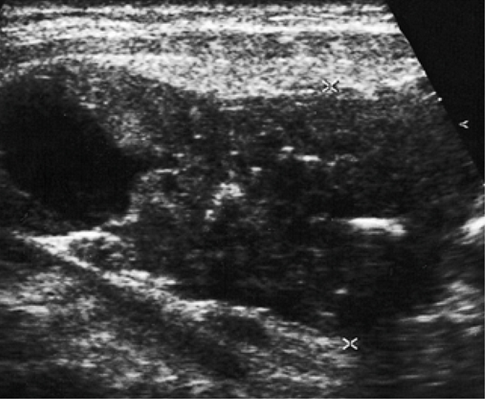

- УЗИ мягких тканей шеи (может прослеживаться наличие опухолевых масс с кистозной трансформацией и кальцификацией);

На данных снимках представлен препарат удалённой доли щитовидной железы с врастающим в неё раком паращитовидных желёз.

Очевидно, что попытка полного отделения опухоли от щитовидной железы технически сомнительна и может привести к разрыву капсулы опухоли, что является очень значимым фактором рецидива рака паращитовидных желёз, в отношении которого потребуется повторная операция. В более запущенных случаях частичному иссечению может подвергаться поражённые опухолевым ростом мышцы, трахея и пищевод. Только полное удаление единым блоком поражённых тканей позволит достичь радикального излечения от рака паращитовидных желёз.